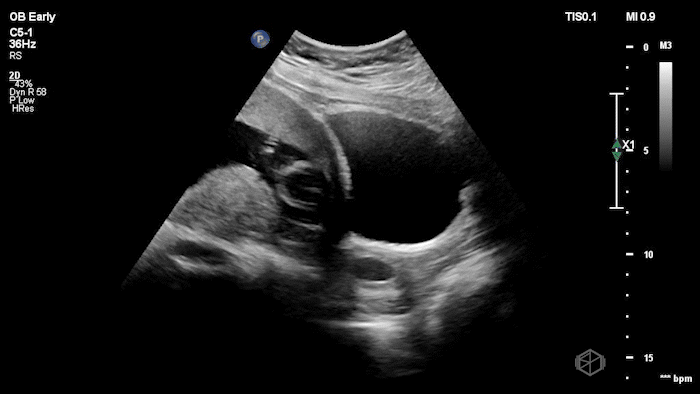

04 - What is the most likely diagnosis and definitive next step for this patient?

Left adnexal complex mass with significant free fluid concerning for ruptured ectopic pregnancy (OB Early setting).